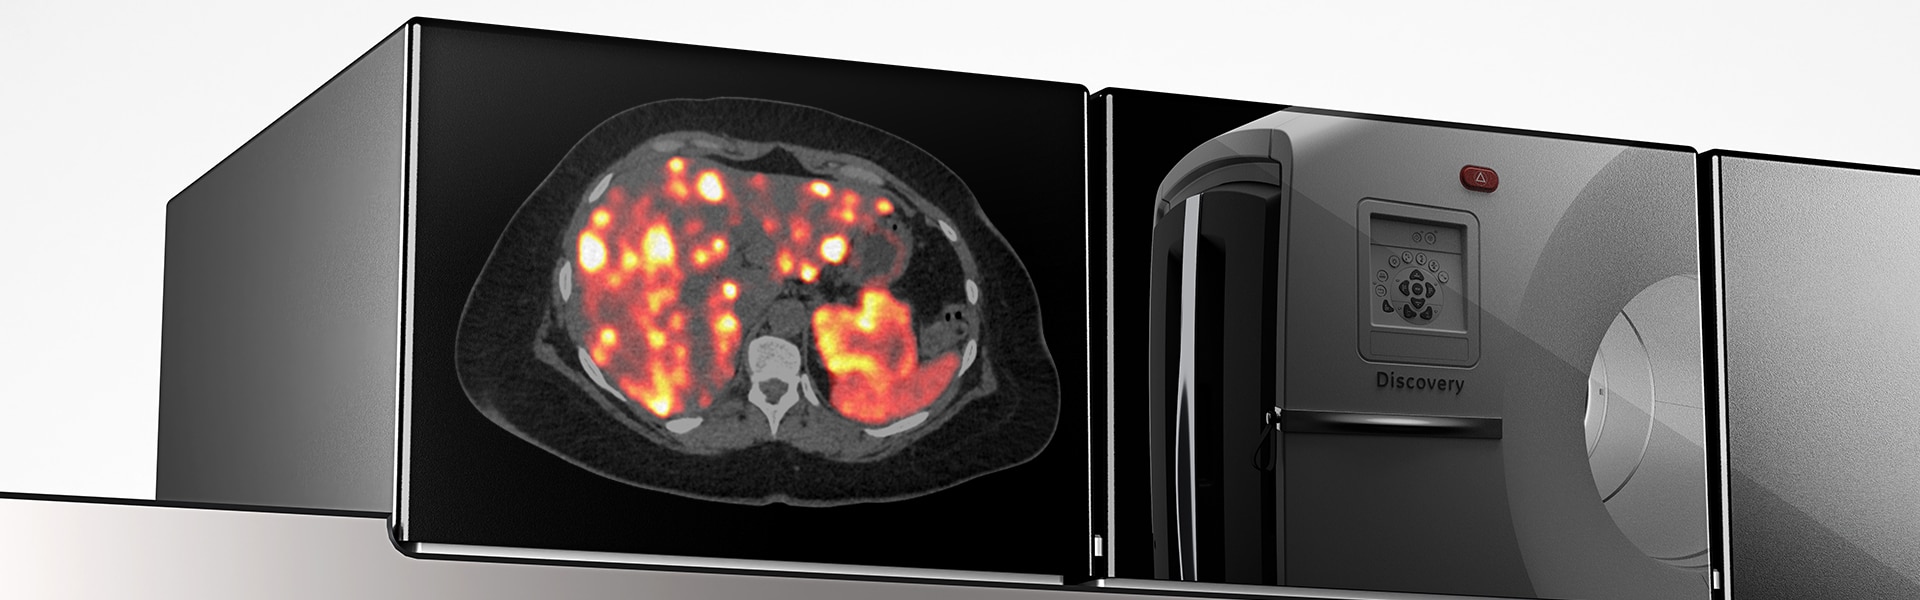

Accurate data points to trusted treatment

- Up to a 2x improvement in image quality (SNR)

- Up to a 2x improvement in quantitative SUV (SUVmean)

SUV accuracy

Up to two times improvement in PET quantitation accuracy (SUVmean) with Q.Clear